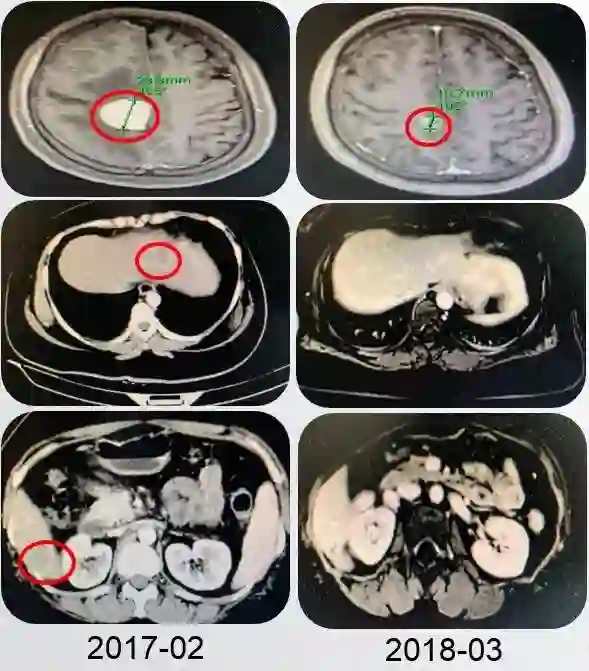

2017年2月,患者自述经常性头痛,间断钝痛,头晕伴有双眼模糊。颅脑MRI示(图2):右顶叶及小脑半球占位,结合患者病史符合脑转移瘤可能性大。

PFS1为14个月。

图2 患者颅脑转移瘤可能性大

结合患者病史、穿刺病理结果,再次重申乳腺癌HER2阳性患者靶向抗HER2治疗的重要意义,最终患者及家属表示同意。二线给予紫杉醇+卡培他滨联合曲妥珠单抗(TXH)方案治疗8周期,具体剂量为:紫杉醇 175mg/m2 静滴d1, 卡培他滨 1000mg/m2 口服bid d1-d14,曲妥珠单抗初始8mg/Kg,后续6 mg/Kg静滴d1,期间给予唑来膦酸预防骨不良事件和给予降低颅内压、保肝等对症治疗。治疗完成后给予全脑放疗DT50Gy/25f。8周期化疗及放疗完成后,综合疗效(图3)评价为部分缓解(Partial Response,PR)。

图3 患者TXH方案8周期治疗和放疗后复查

患者8周期TXH方案化疗完成后,给予H方案维持治疗,期间因个人原因停用曲妥珠单抗。2018年9月复查肝脏病灶较前进展,综合疗效评价为病情进展(progressive disease,PD)。结合患者病史,行长春瑞滨联合曲妥珠单抗(NH)方案三线治疗,具体用法为:长春瑞滨25mg/m2静滴d1,1/7d,曲妥珠单抗6mg/kg 静滴d1,1/21d。2019年3月进行综合疗效评价(图4)为部分缓解(partial response,PR)。治疗完成后给予曲妥珠单抗维持治疗至今,期间定期复查未见明显新发转移或疾病进展征象。

PFS2为19个月,截至当前,患者总生存期为61个月。

图4 患者NH方案治疗后复查